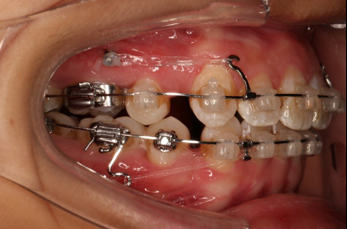

2016.10.31  初戴,0.013cu-niti2017.1.13  上颌加TPA,U56间斜形植入韩国庆北1312-08种植钉,上下0.16cu-niti

2017.02.16  上下0.014*25 cu-niti,50g 拉尖牙远中

2017.04.28

2017.04.28  上0.016*25ss 13、23近远中约5度 v形曲,下0.017*25ss

2017.05.26  磨牙近中倾斜,下颌36、46加power arm

2017.07.25

2017.07.25  上前牙加颈部弹力线